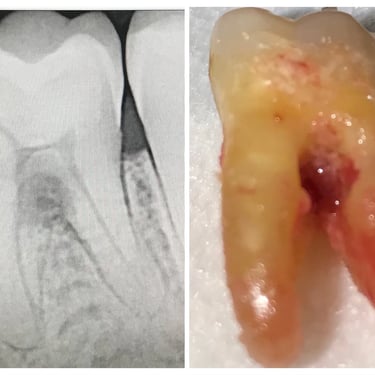

Pulpitis Crónica Hiperplásica

La pulpitis crónica hiperplásica es una inflamación de la pulpa con crecimiento excesivo de tejido pulpar a través de una caries abierta.

Los pacientes notan un tejido rojo que sobresale de la cavidad dental.

El tratamiento incluye la eliminación del tejido afectado y un tratamiento de conducto. Es crucial tratar la caries para evitar infecciones adicionales.